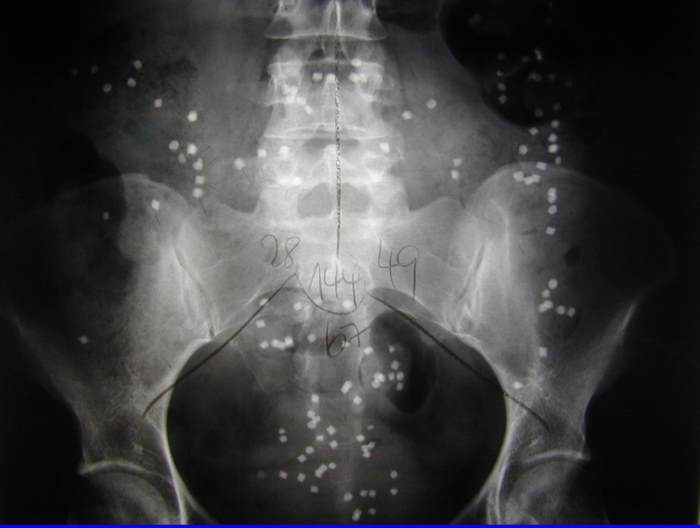

6. Messung der Transportfunktion des Darmes (Kolontransitzeit)

Bei einigen Patienten besteht eine langjährige, hartnäckige Verstopfung, die häufig schon in der Kindheit beginnt. Die Patienten können häufig ohne Abführmittel keinen Stuhl entleeren. In einigen dieser Fälle liegt dieser Problematik eine Transportstörung des Darmes zugrunde. Zur Überprüfung erhalten die Patienten Kapseln mit sogenannten "Markern". 6 Tage später wird eine Röntgenaufnahme des Bauches angefertigt. Bei einer Transportstörung findet sich eine Verteilung der Marker im gesamten Dickdarm. In einigen Fällen sammeln sich die Marker auch im Enddarm und im Mastdarm. Natürlich dürfen während dieser Untersuchung über mehrere Tage keinerlei Abführmaßnahmen durchgeführt werden. Ein spezieller Test ermöglicht auch den Nachweis von Transportstörungen im Dünndarm, die sehr selten sind.